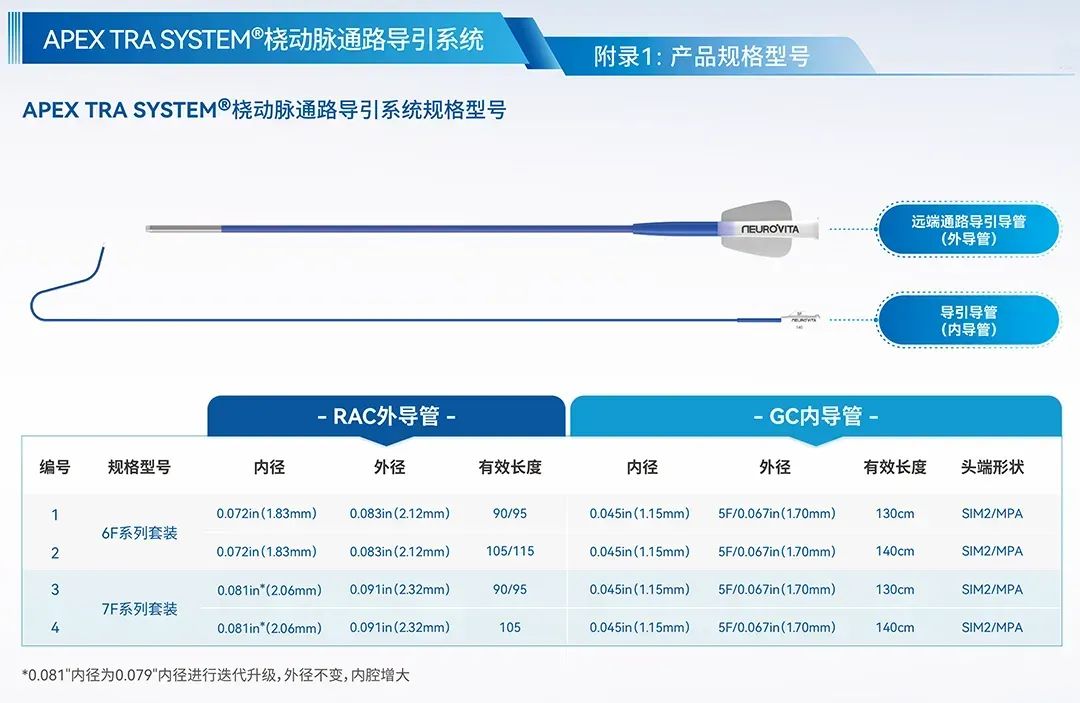

赛诺经桡通路系列产品

桡动脉通路导引系统产品介绍

针对不同规格,更合理的分段设计:

赛诺经桡专用APEX TRA®导管与常用颈动脉支架匹配性表